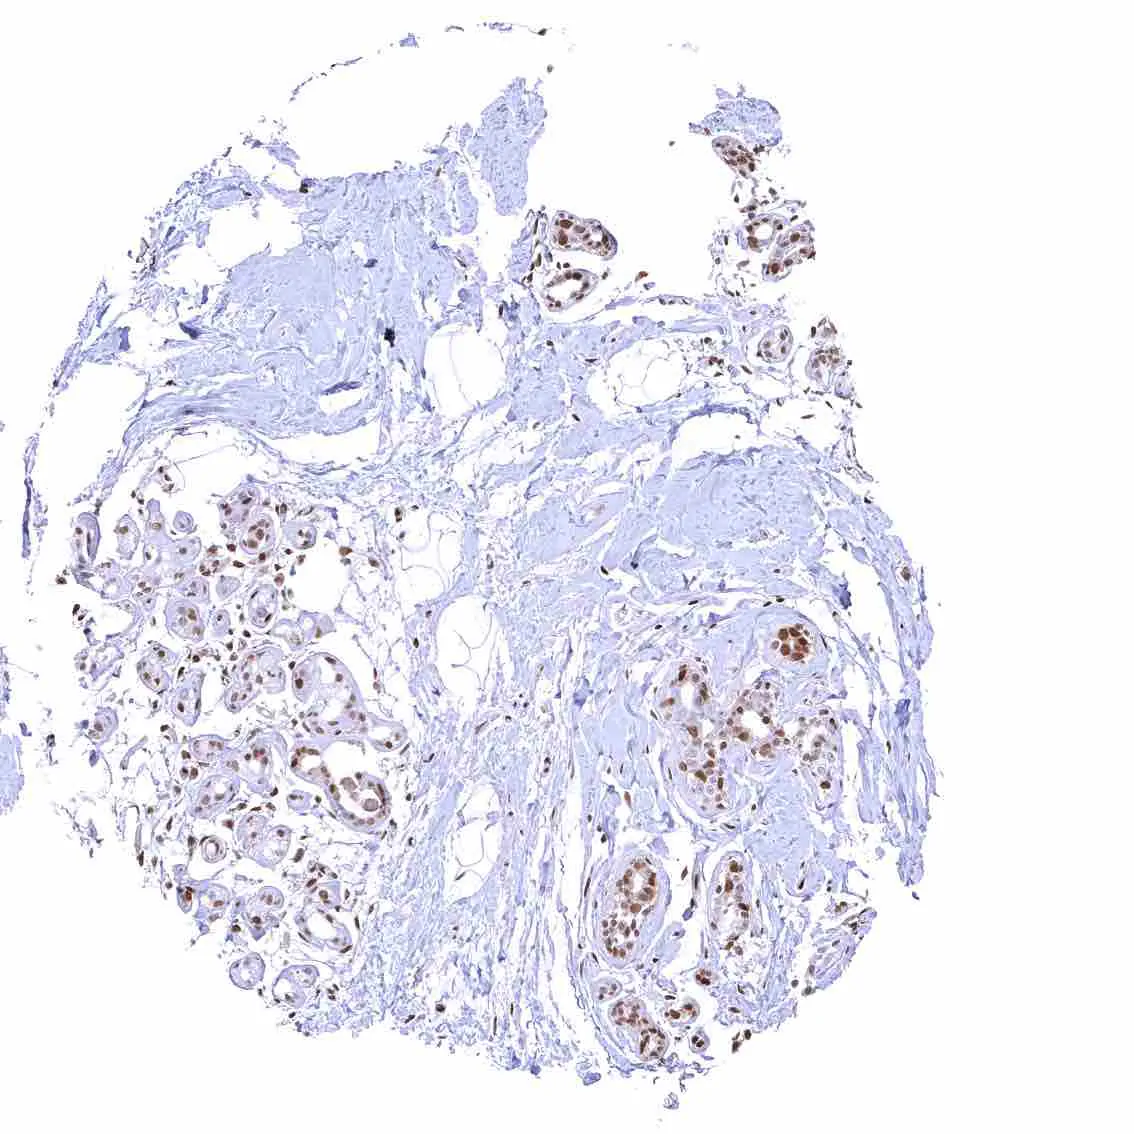

Breast – Moderate to strong nuclear p27 positivity of a large fraction of glandular epithelial cells.